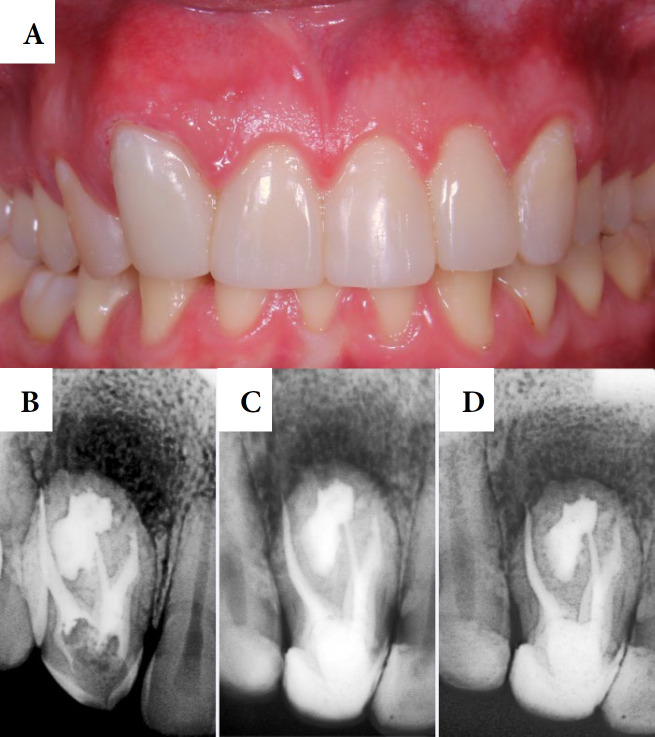

牙凹是一种发育畸形,是由牙釉质器官在组织钙化之前内陷到牙乳头内部区域引起的。本报告的目的是讨论一个临床病例的根管治疗#12牙,使用生物陶瓷封口剂。口腔外检查显示解剖不典型,活力和敲击试验阴性,触诊试验阳性。邻近牙龈黏膜水肿。根据临床和断层检查结果,诊断为牙髓坏死合并慢性根尖周脓肿和Oehlers型牙槽内陷。在第一阶段,在手术显微镜(OM)和超声金刚石尖端的帮助下,使用球形钻头进行手术。找到了四条管道,并对其进行了部分清理和药物治疗。在第二阶段,进行了牙镜测量和镍钛器械化学机械制备。冲洗液为2.5%次氯酸钠。用氢氧化钙糊剂填充根管,暂时封闭根管腔。在第三次治疗中,超声冲洗进行最后的清洗,使用经典的单锥技术用Bio-C密封剂填充根管。在6个月的随访中,牙齿无症状,x线摄影显示明显的骨修复。结论采用断层扫描、手术显微镜、超声冲洗、生物陶瓷封口剂等流量较大的材料,提高了临床病例的成功率。

Dens invaginatus is a developmental malformation that is caused by the invagination of the enamel organ into the internal region of the dental papilla before tissue calcification. The aim of the present report is to discuss a clinical case of endodontic treatment of tooth #12, using bioceramic sealer. The extraoral examination revealed atypical anatomy, while vitality and percussion tests were negative, palpation test was positive. Edema was observed in the adjacent gingival mucosa. Based on clinical and tomographic findings, the diagnosis was pulp necrosis with chronic periapical abscess and Oehlers' type II dens invaginatus. In the first session, access surgery was performed with spherical drills with the aid of an operating microscope (OM) and an ultrasonic diamond tip. Four canals were located, and they were partially debrided and medicated. In the second session, odontometry and chemical-mechanical preparation with nickel-titanium instruments were performed. The irrigation solution was 2.5% sodium hypochlorite. The root canals were filled with calcium hydroxide paste and the chamber was temporarily sealed. During the third session, ultrasonic irrigation was applied for final washing and the root canals were filled with Bio-C sealer using the classic single-cone technique. At 6-month follow-up, the tooth was asymptomatic and the radiography revealed significant bone repair. It was concluded that tomography, operating microscope, ultrasonic irrigation, and materials with greater flow, such as bioceramic sealers, enhanced the clinical success of the clinical case.